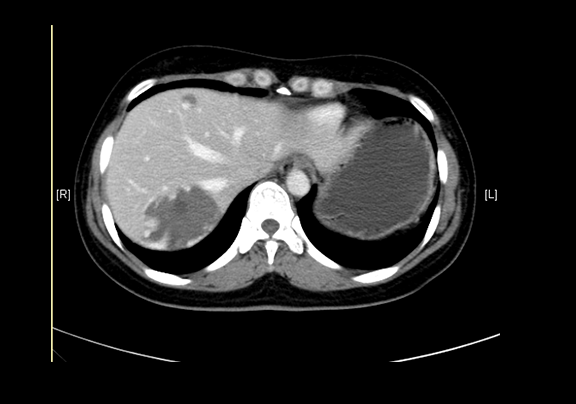

术前CT检查:动脉期

现病史:患者查体发现肝血管瘤半年,无腰背部放射痛、皮肤巩膜黄染、恶心、呕吐、寒战、高热、腹泻、血便、咳嗽、咳痰、胸闷、气短、尿频、尿急、尿痛、血尿,未予治疗。行上腹部增强CT示:肝血管瘤。

辅助检查: 下腹部增强CT示:肝内多发血管瘤可能性大,肝囊肿